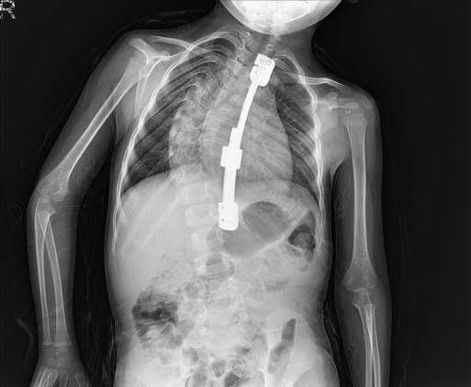

Doğuştan skolyozu (omurga eğriliği) olan Eymen Yasir Kapucu, iki kez devlet hastanesinde skolyoz ameliyatı oldu ancak ameliyatlar başarısızlıkla sonuçlandı. 15 yaşına kadar altı ayda bir ameliyat olması gereken Eymen'in doktorları ise; Eymen çok küçük olduğu için bu ameliyatları kaldıramayacağını söylüyor.

Eymen'in bir ameliyatla tedavisi mümkün. Ama bu sistem (rod sistem) yalnızca özel hastanede yapılıyor. Asgari ücretle geçinen ailenin ise minik Eymen'i ameliyat ettirebilecek ekonomik gücü yok. ailenin yakınları, aileye yardım elinin uzanmasını diliyor.